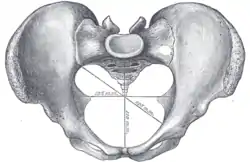

Pelvis, with dotted line marking linea terminalis | |

The linea terminalis or innominate line consists of the pubic crest, pectineal line (pecten pubis), the arcuate line, the sacral ala, and the sacral promontory.[1]

It is the pelvic brim, which is the edge of the pelvic inlet. The pelvic inlet is typically used to divide the abdominopelvic cavity into an abdominal (above the inlet) and a pelvic cavity (below the inlet). Sometimes, the pelvis cavity is considered to extend above the pelvic inlet, and in this case the pelvic inlet is used to divide the pelvic cavity into a false (above the inlet) and a true pelvis (below the inlet).

Diameters of superior aperture of lesser pelvis—female

Diameters of superior aperture of lesser pelvis—female Female pelvis